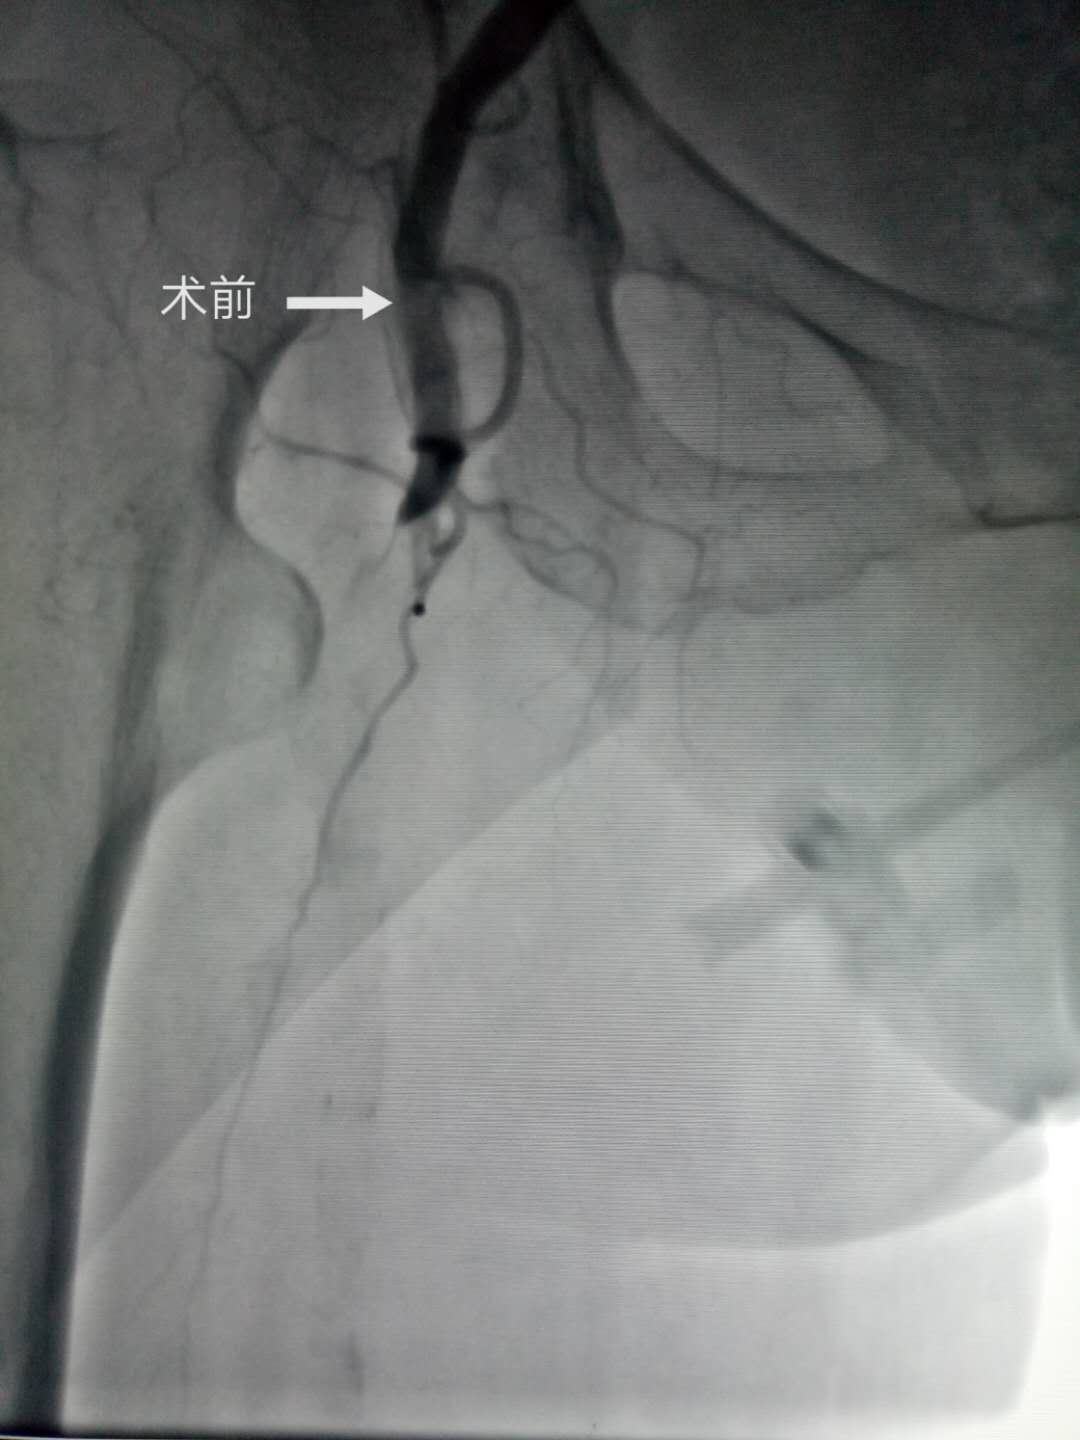

患者女性,90岁,以“间断胸闷、气短20年余,右下肢冰冷1天”之主诉入院,查体:右下肢皮肤苍白,皮温低,足背动脉搏动消失。彩超提示右下肢股动脉血栓形成,且造成管腔闭塞可能。患者为超高龄女性,体重只有38公斤,同时合并2型糖尿病、冠心病、心力衰竭等疾病,属于出血超高危险患者。现急性右下肢动脉血栓形成,需要急诊介入治疗,否则有肢体坏死的风险。在郭瑄主任医师主持下,经全科积极讨论确定右下肢动脉血栓形成的微创治疗方案。认真完成术前准备后,充分告知家属手术风险,由郭瑄主任医师、尚粉青副主任医师在介入室配合下于2019年4月10日下午在局麻下行右下肢动脉血管造影术+血栓抽吸术+动脉血栓溶栓术,手术过程顺利,术后患者右下肢供血明显改善。